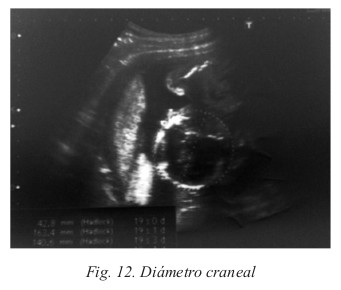

A partir de las 7 semanas podemos diferenciar el polo cefálico, las extremidades y la bolsa amniótica del embrión; alcanzando éste los 25-27 mm de tamaño (Fig. 11). En este momento, el parámetro óptimo para datar la gestación es la medición de la longitud craneocaudal. A partir de la semana 12, se utilizará la medición del diámetro biparietal (Fig. 12) para conocer la edad real del embarazo, y en la semana 20 la longitud del fémur (Fig. 13).